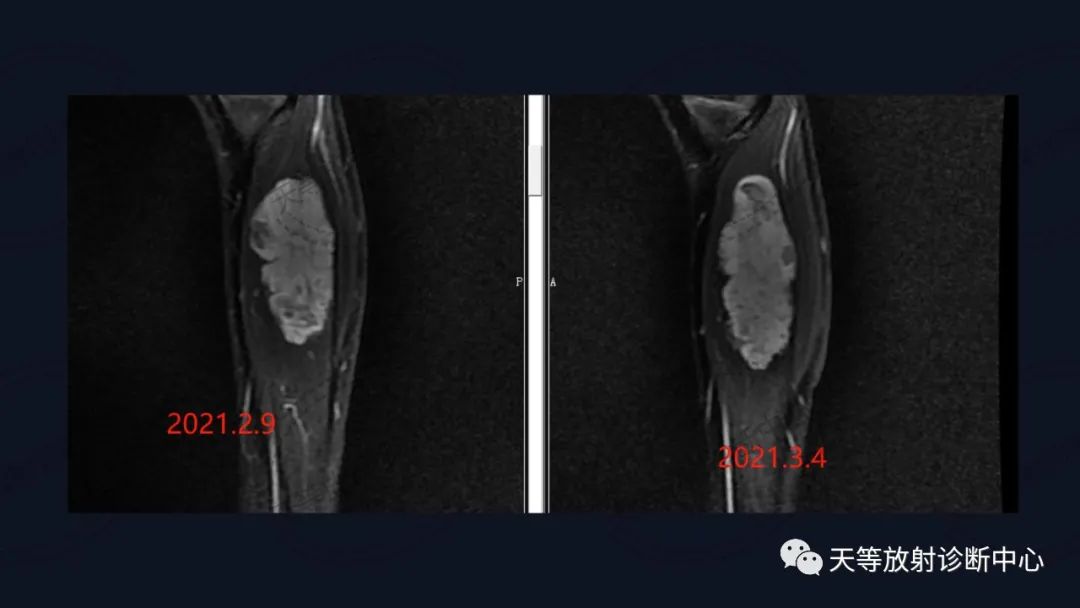

上图:压脂序列肿块椭圆形,内部见细小分隔,血管流空信号。

前后两次对比观察,病灶略有增大。